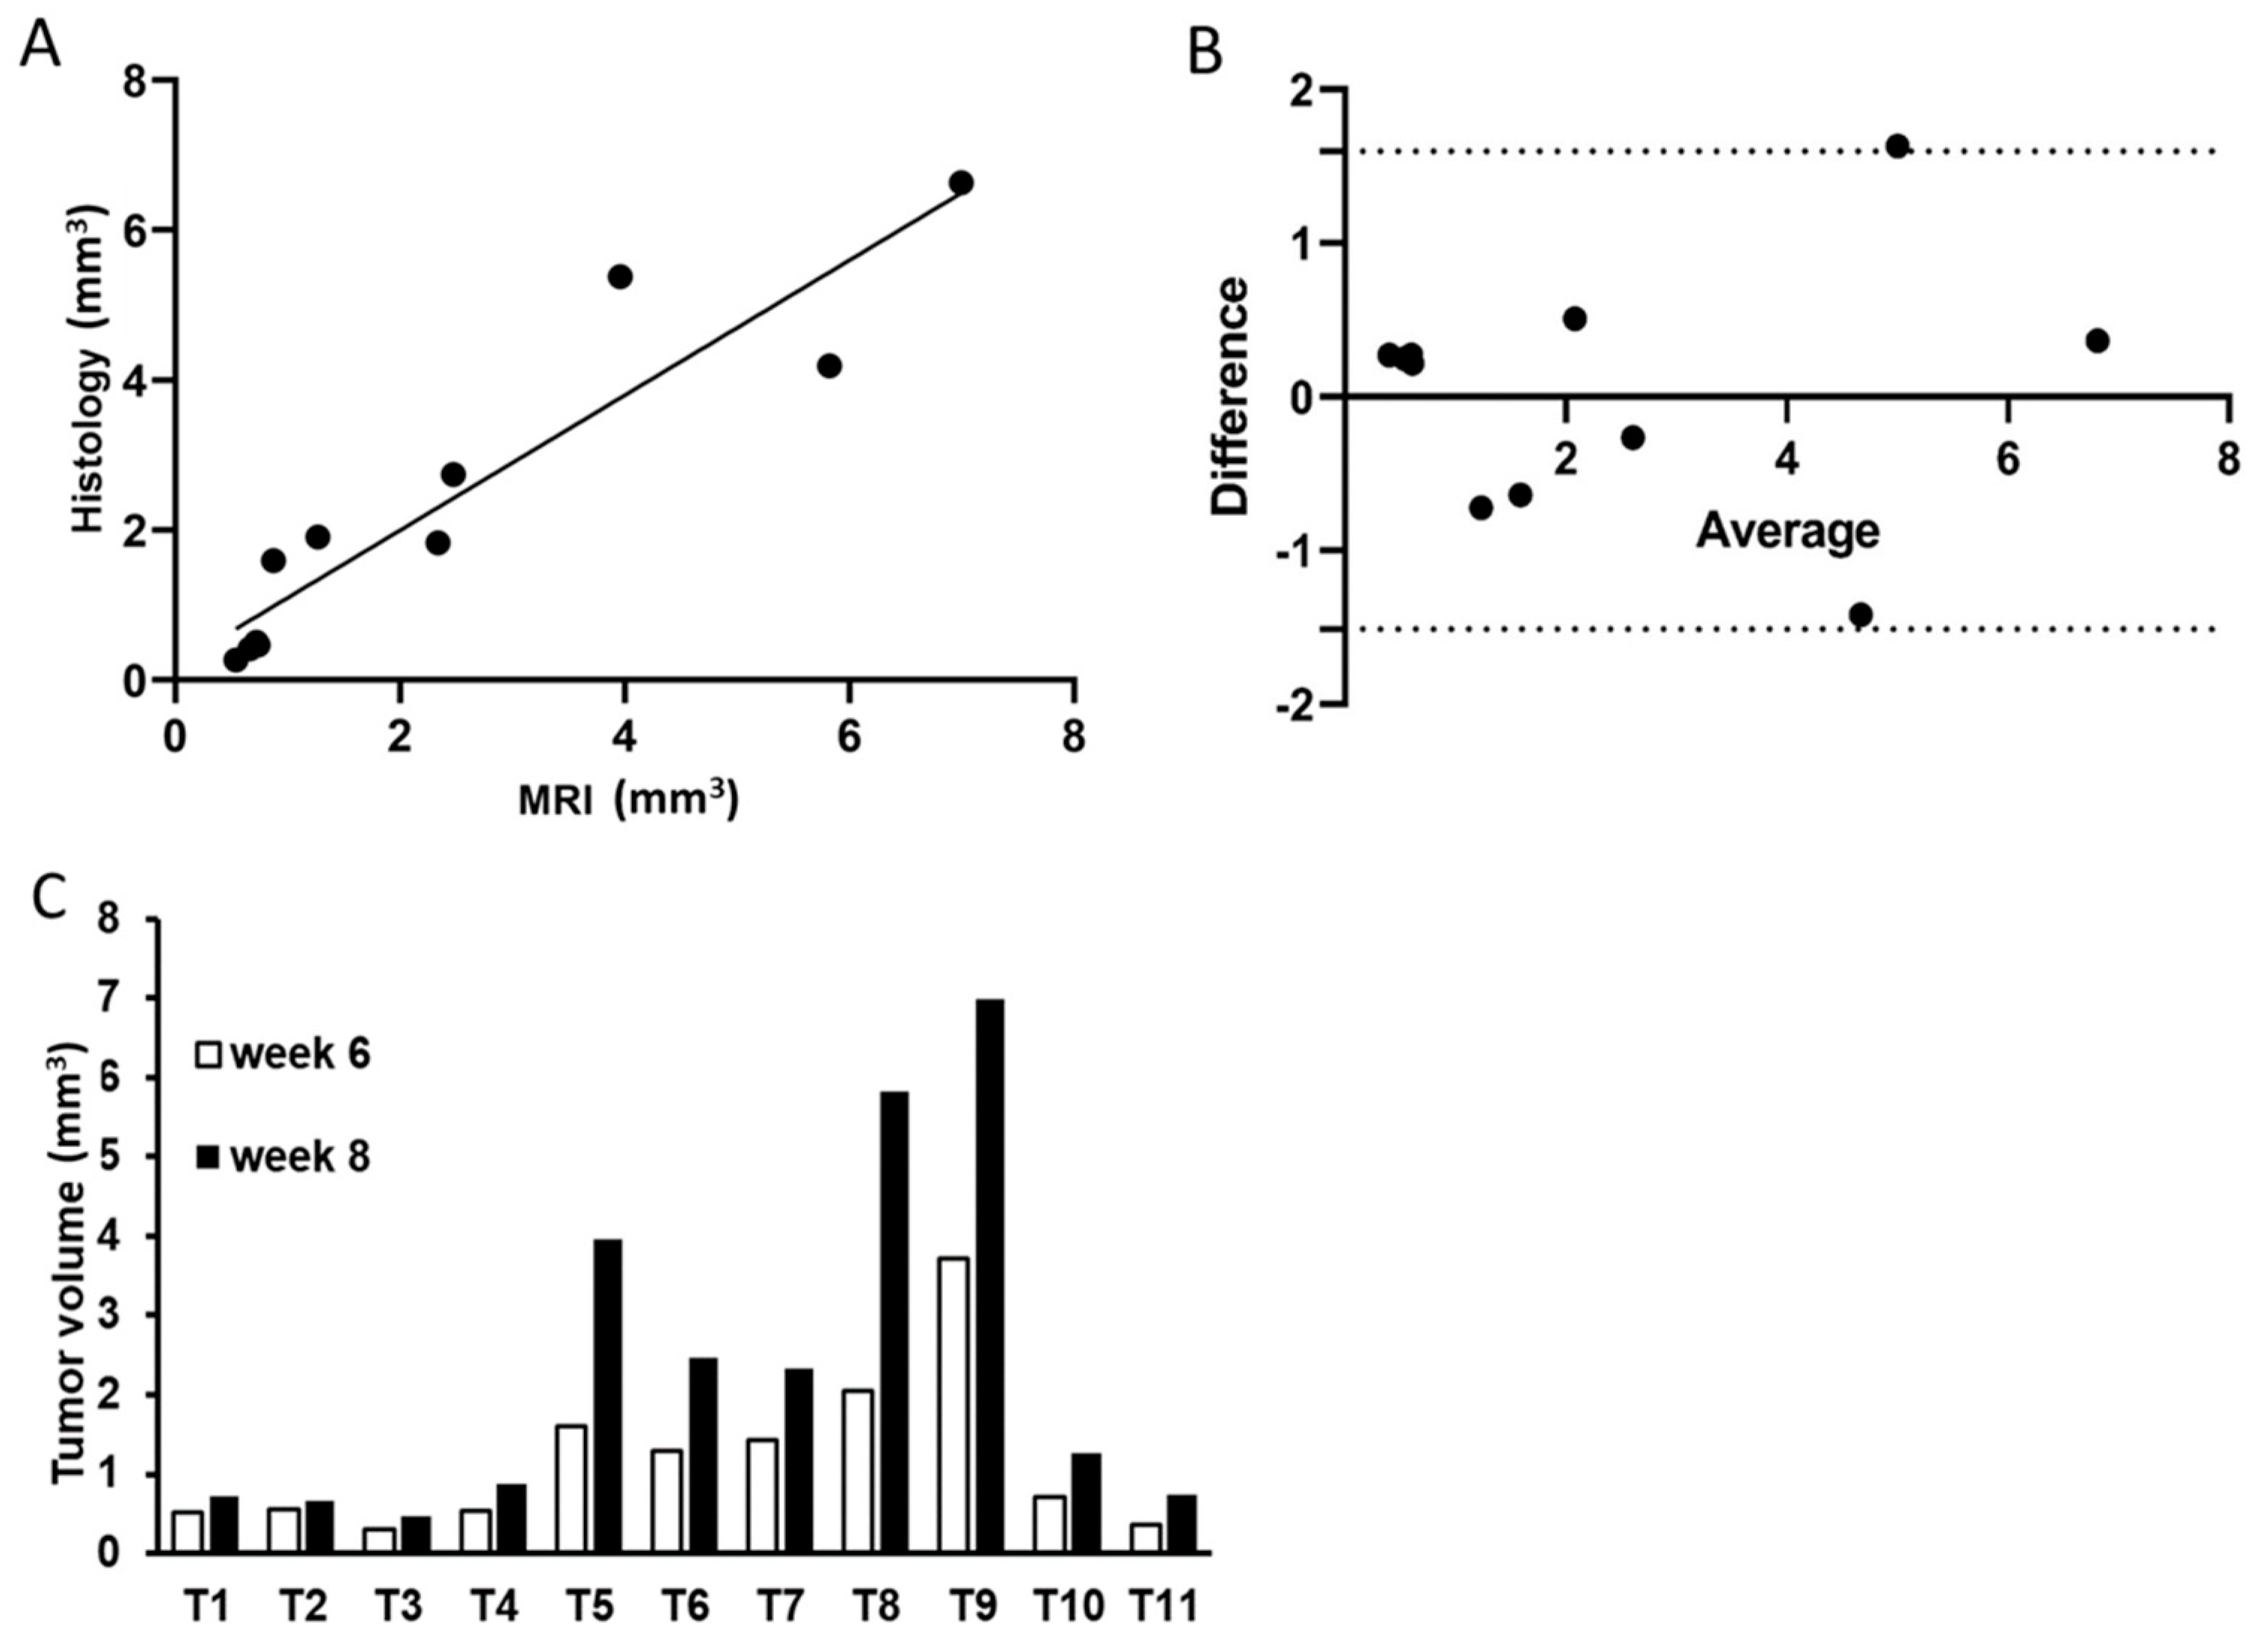

3.3. MRI Performance in Assessing Tumor Growth